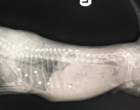

Röntgen felvételeket is készítettek róla. Ekkor valami szörnyű dolgot fedeztek fel az orvosok. Ebben a kis testben összesen 18 sörétes puskából származó golyót találtak.

Luckynak szerencséje volt, mert egyik golyó sem érte a csontjait, sem létfontosságú szerveket.

Mivel a kutya nagyon fiatal volt, még nem tudták elaltatni ezért nem tudták kioperálni a golyókat. Meg kellett várni amíg a kutyus kicsit idősebb lesz, hogy kibírja majd az altatást.